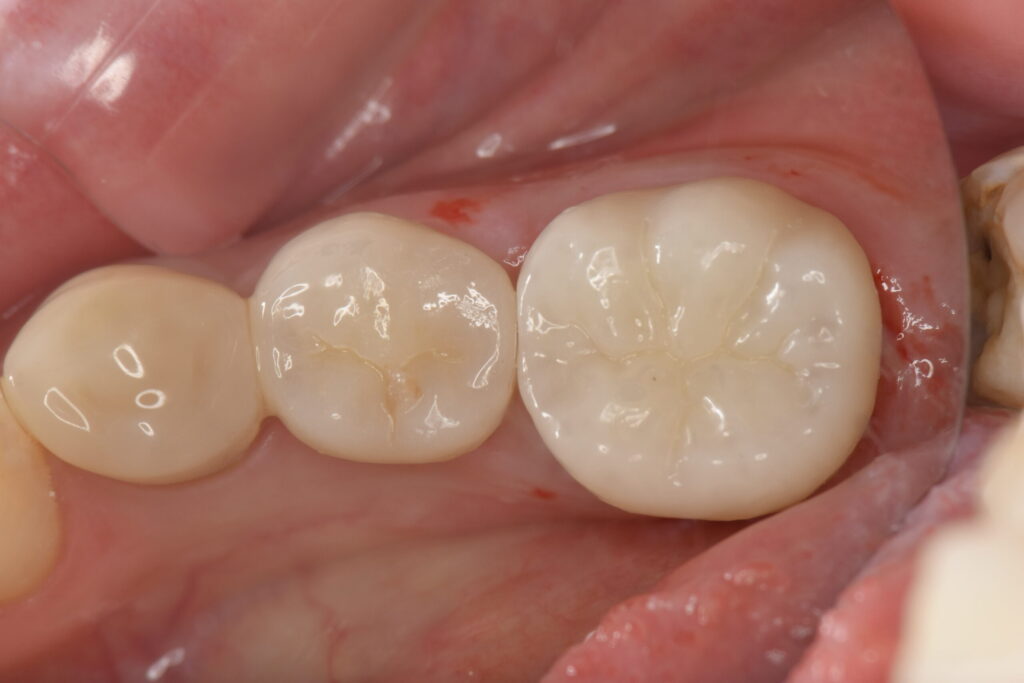

患者様は精密治療を希望されたため、まずは左下の虫歯をジルコニアセラミックで被せ直しました。

奥歯にセラミックを選ぶ最大の利点は、精密な適合性による「再発防止」です。銀歯は接着剤が唾液で溶けやすく、長年使ううちに歯との間に隙間が生じ、そこから虫歯が再発するリスクを抱えています。一方、セラミックは歯と化学的に強力に接着するため、細菌の侵入を許さず、歯の寿命を大幅に延ばすことができます。

また、歯周組織への影響も見逃せません。セラミックは表面が極めて滑らかで、汚れ(プラーク)が付きにくい性質を持っています。これにより、銀歯に比べて周囲の歯ぐきが炎症を起こしにくく、清潔な口腔環境を保ちやすくなります。

さらに、金属アレルギーの心配がない「メタルフリー」である点も重要です。金属の溶け出しによる体への蓄積や、歯ぐきの黒ずみを防げるため、健康意識の高い方にとって非常に価値のある選択肢となります。